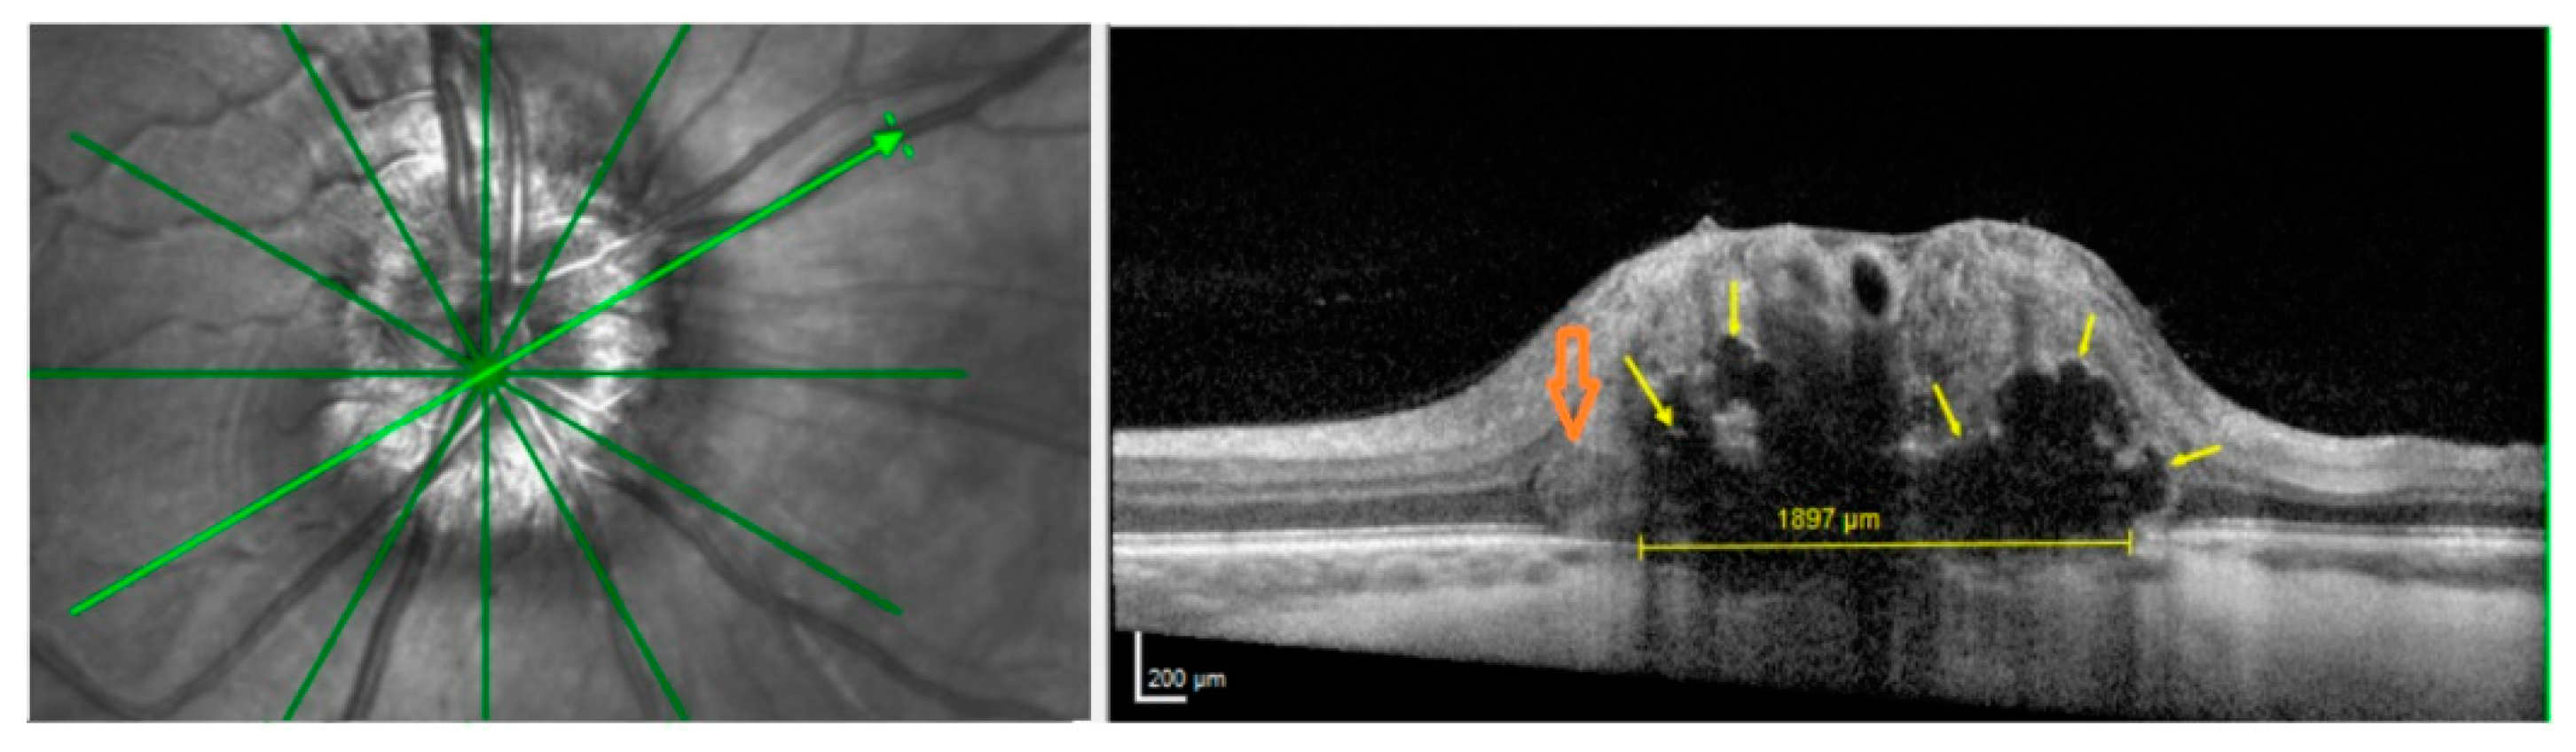

3.2. ODD, HL and PHOMS